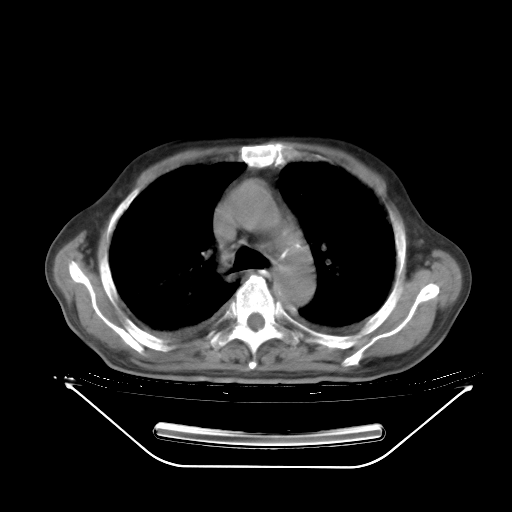

5月9日肺部CT(在4月27日齐鲁医院肺部CT描述部分肺组织磨玻璃样改变,12天后肺组织广泛磨玻璃样改变)

2009年5月9日肺部CT

大致读了系列胸部CT:纵隔窗无明显异常,肺窗:从4、27至今:主要是双肺中下野外带可见毛玻璃样改变,目前处于急性肺泡炎阶段,至于原因考虑1、结替组织或胶原血管性疾病所致?2、恶性疾病如恶组在肺部所致的表现或细支气管肺泡癌?3、药物或其它原因如肺蛋白沉着症所致肺泡炎目前不太可能?总之,明天就去请我院的呼吸科、感染科、血液科和临免专家会诊哈。